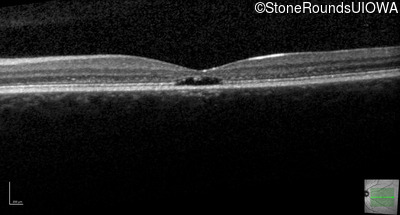

Age at visit: 17 years

OD OS

This 17 year old female first noted problems with her visual acuity around age 13 when she had trouble seeing the projector from the back of the classroom.

Age at visit: 16 years

Age at visit: 18 years

Age at visit: 22 years